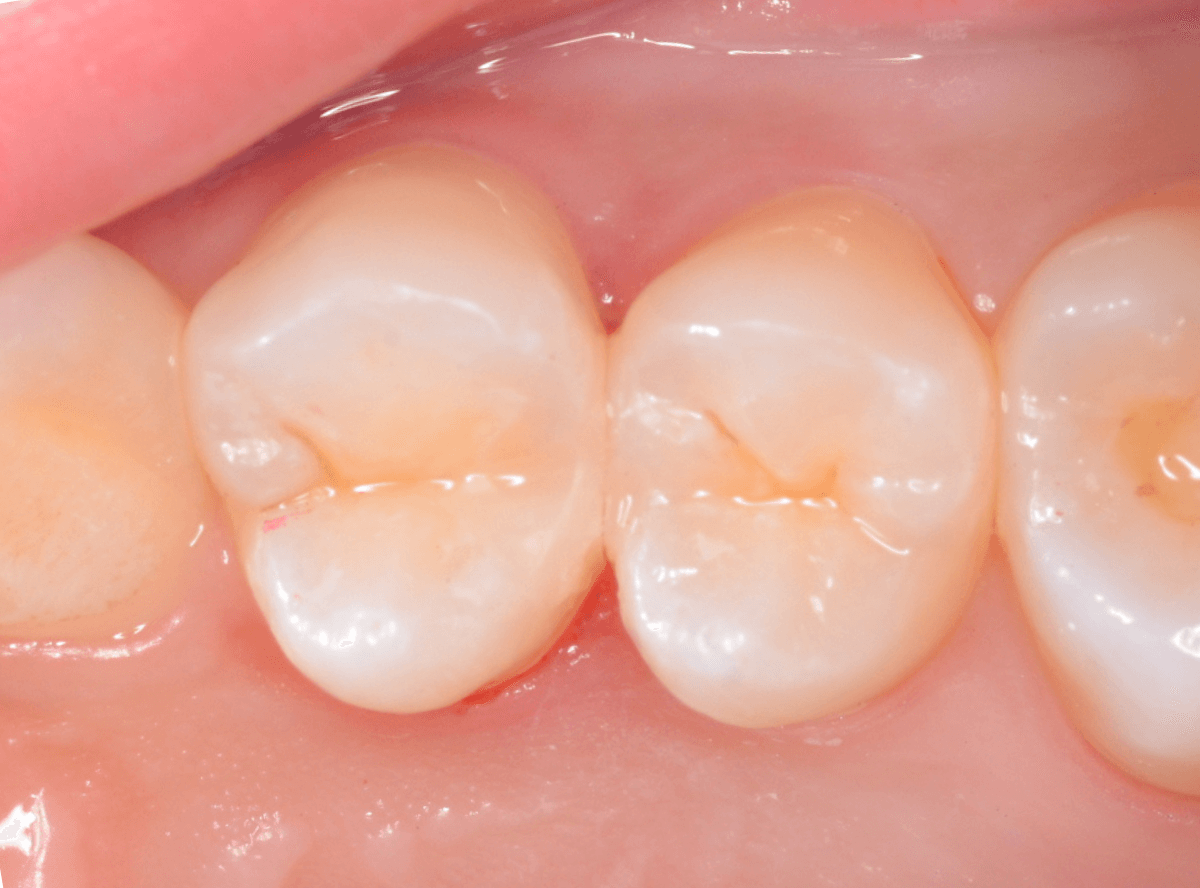

虫歯の部分を全部除去したところです。

少し中で広がっていました。早めに治療ができてよかったです。

今回は、歯を削った部分にレジンをつめる簡単な処置ですみました。